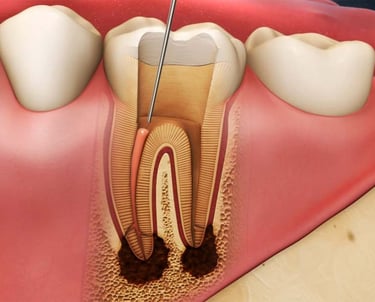

Es el procedimiento para limpiar, desinfectar y sellar los conductos internos del diente cuando la pulpa está infectada o inflamada. Es esencial para salvar el diente.

Tratamiento de Conducto

Se trata de una infección en el extremo de la raíz del diente que forma una acumulación de pus. El tratamiento incluye la limpieza y desinfección del conducto radicular y, en algunos casos, el drenaje del absceso.

Tratamiento de Absceso Periapical